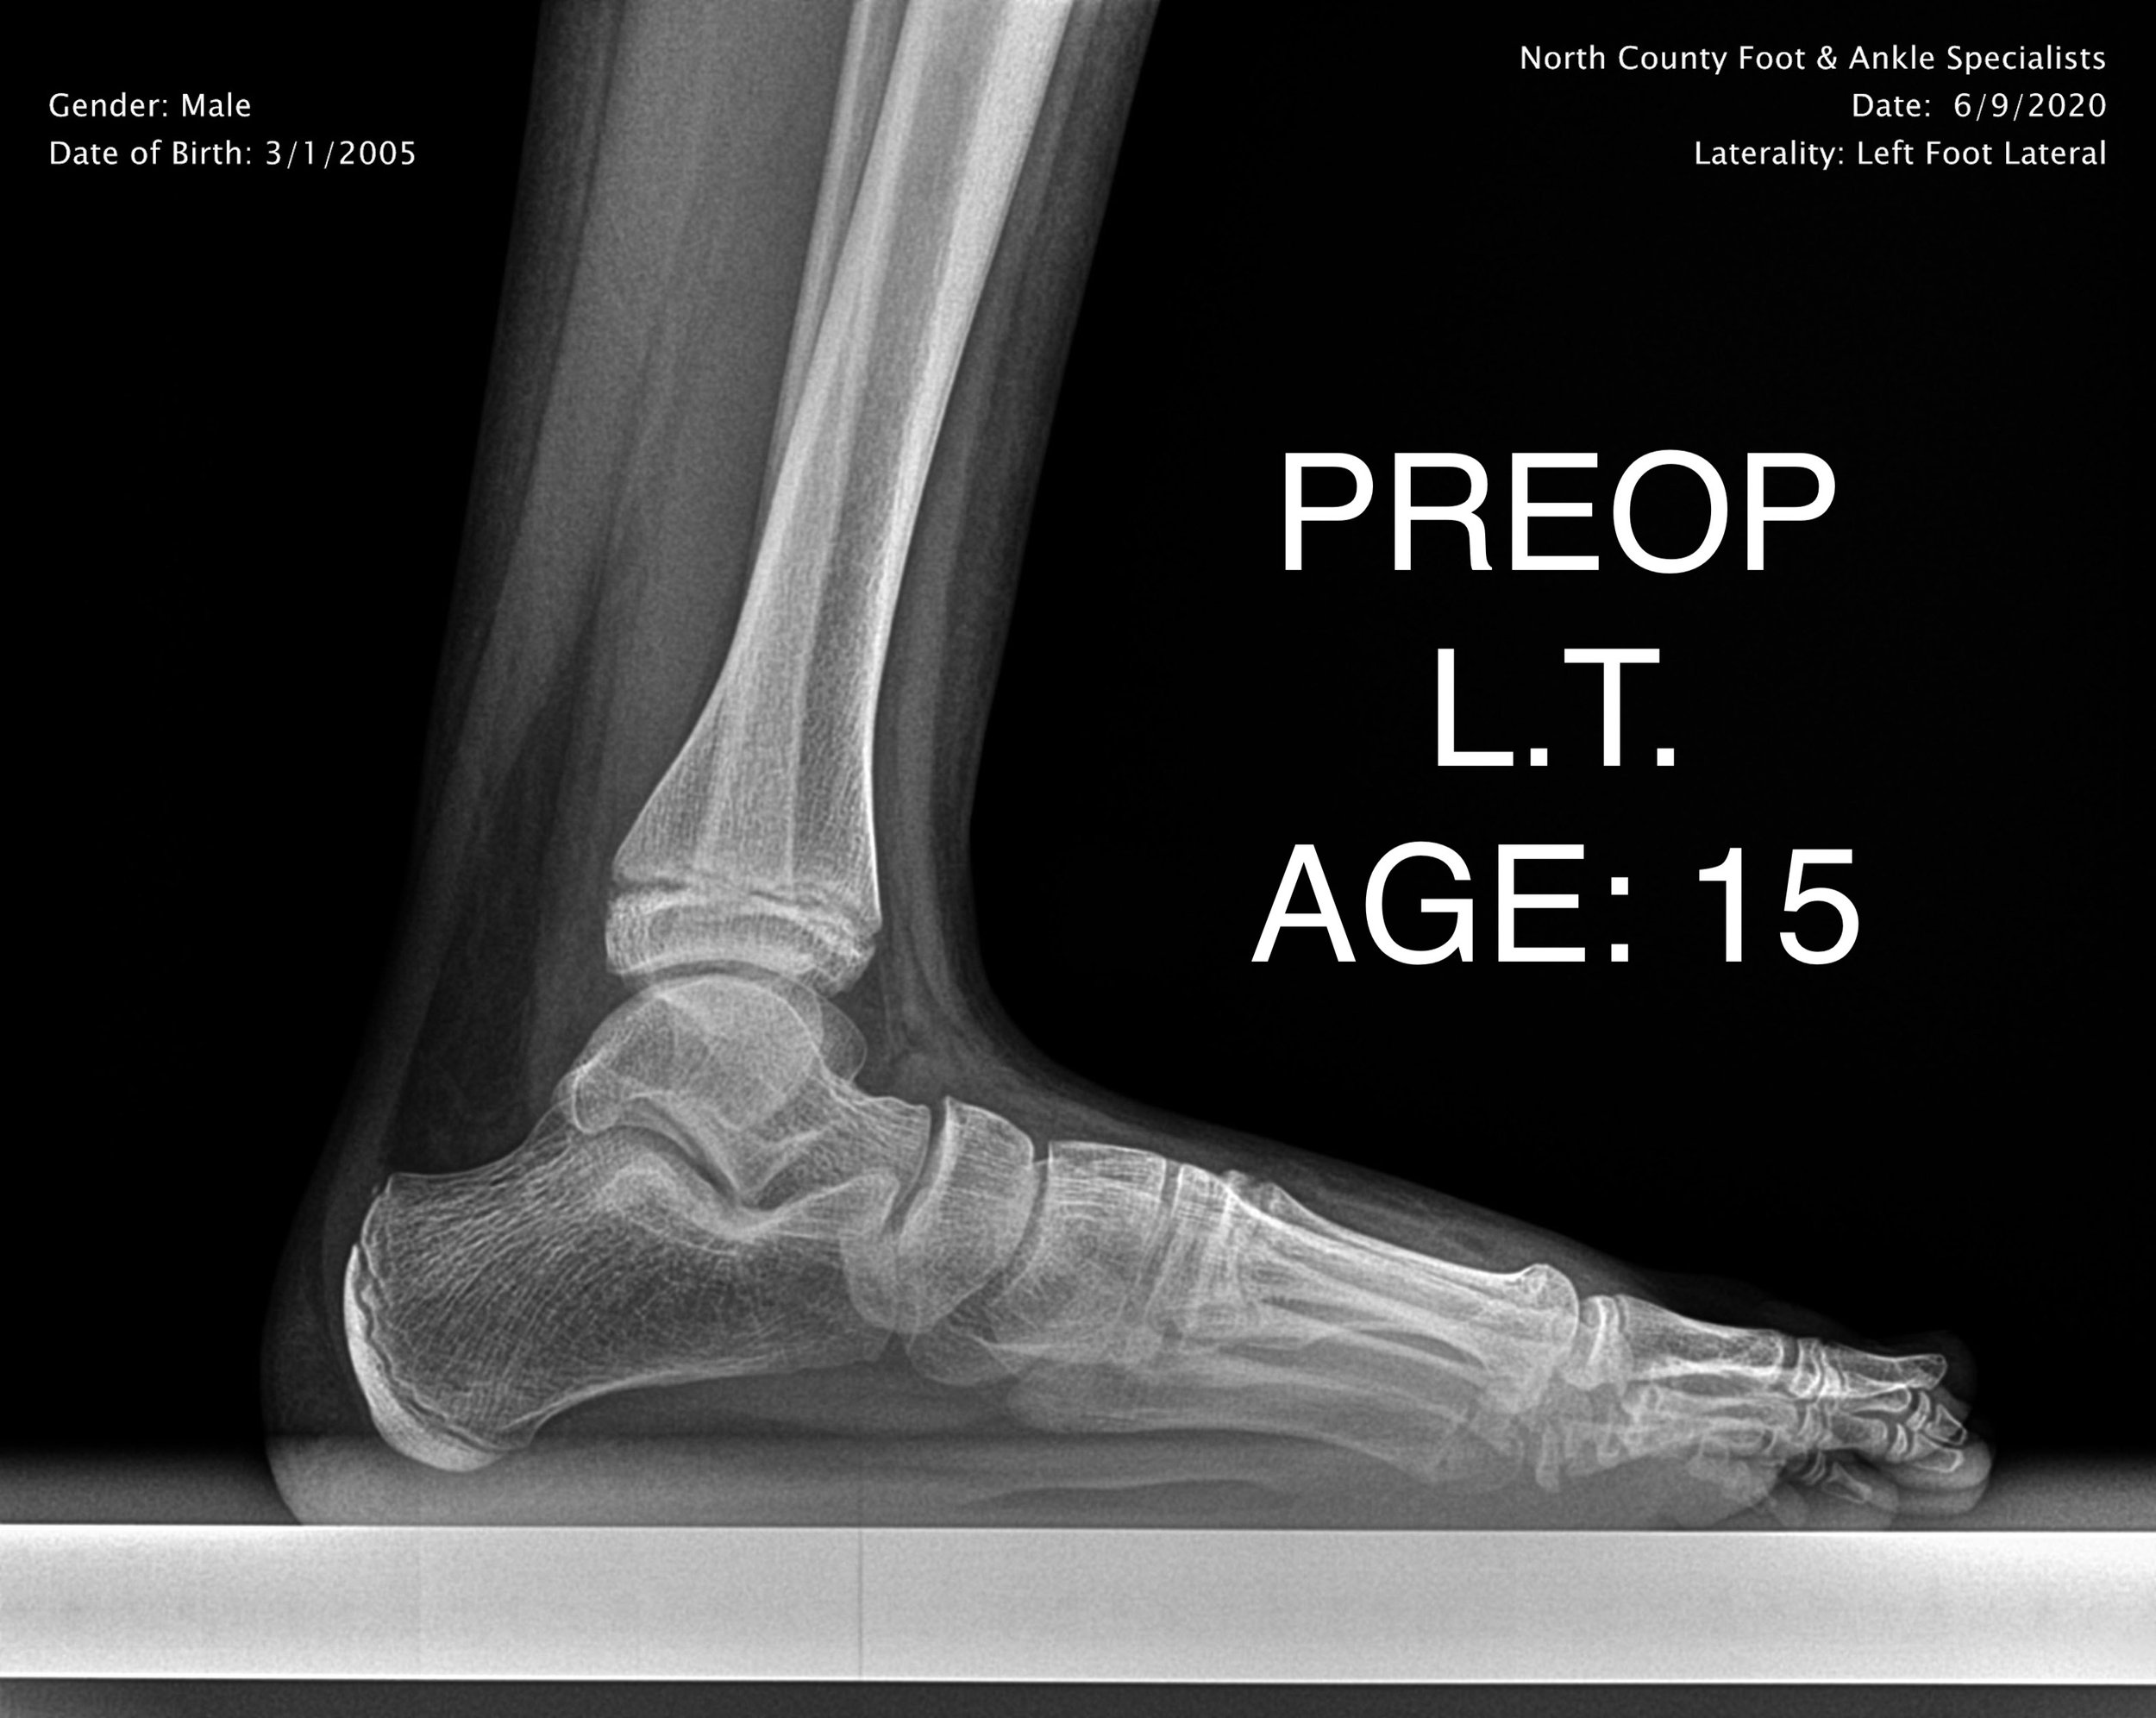

PEDIATRIC FLAT FOOT